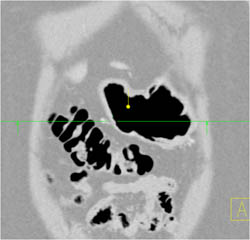

Antral Cancer